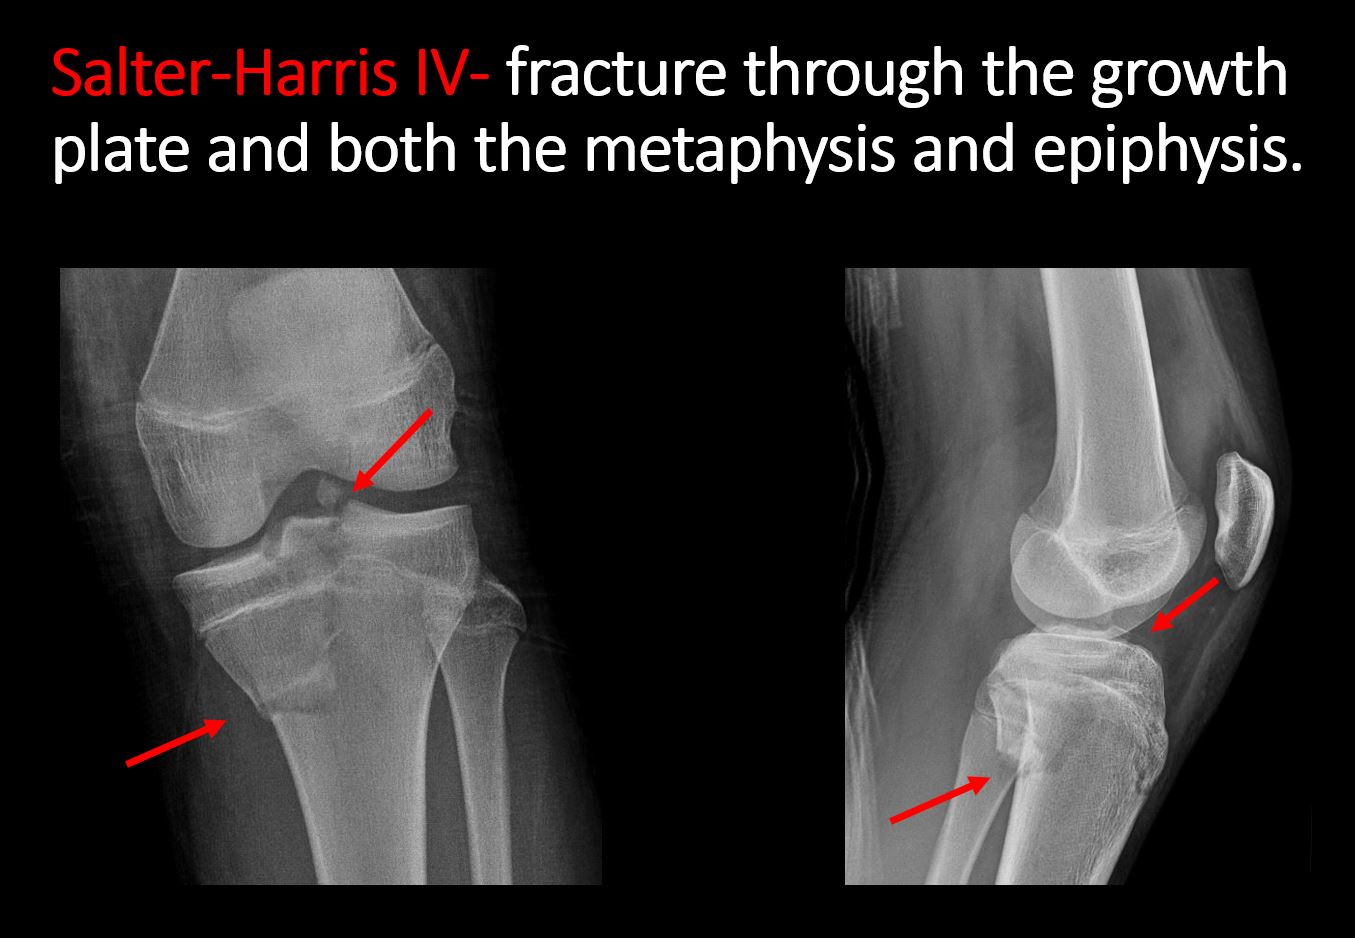

There is a fracture through the metaphysis, physis, and epiphysis which extends into the joint space with or without angulation or displacement (S-H IV). [Yes/No]